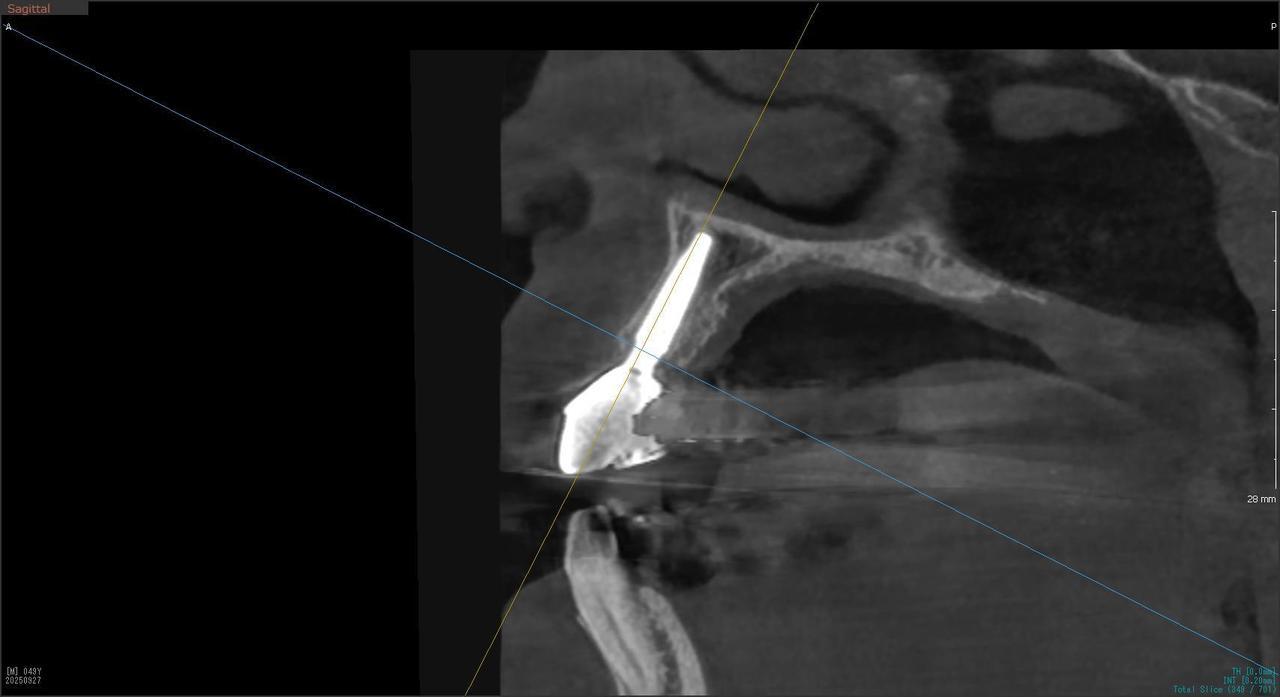

4.右上5が折れたために、インプラント抜歯即時埋入をおこなったインプラント治療のケース。

Before

枚方市のインプラントの症例

After

T・T 様 女性 40代

症状としては、 右上5番の歯が折れてしまった。保存することは不可能な状態であった

治療法としては、患者様は、歯が折れたことを主訴に来院。インプラント治療を希望したため、抜歯した当日に、インプラント埋入をおこなって、骨欠損部には人工骨を補填した。1か月半後にインプラントが骨と結合していることを確認できたため、光学印象を行い、2か月後に、最終補綴物として、アバットメントとジルコニアクラウンの装着を行いました。

治療結果としては、抜歯したと同時にインプラントを埋入することで、抜歯した穴が自然に治る過程で、インプラントの骨結合と組織の治癒が同時に行われるために、2か月という治療期間で治療を終了することができたことと、機能面・審美面でも回復を行うができた。

治療の期間・回数:約2か月、インプラント抜歯即時埋入から最終補綴物装着まで4回

治療の価格:352,000円(税込)

治療費の内訳:インプラント基本料(フィックスチャー及び手術費用、投薬費用、レントゲン費用、インプラント上部費用(アバットメントおよびジルコニアクラウンの費用用)330000円(税込み)。オプション、抜歯即時埋入加算(人工骨費用を含む) 22000円(税込み)

治療のリスクや副作用:手術後に、痛みや腫れ、出血、合併症などを引き起こす可能性があります。噛む感覚がご自身の歯と異なる場合があります。見た目がご自身の歯と異なる場合があります。手術後にメインテナンスを継続しないと、インプラントが抜け落ちる可能性があります。